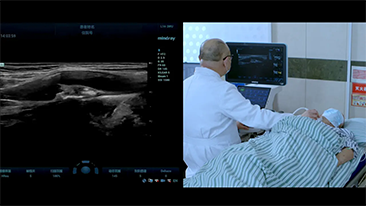

La gamme d'imagerie gÊnÊrale Resona de Mindray aide les cliniciens à obtenir des rÊsultats de diagnostic plus prÊcis et des traitements plus efficaces gr?ce à une gamme de sondes complète et à des outils cliniques avancÊs efficaces.

L'environnement mĂŠdical devient de plus en plus complexe, avec toujours plus de cas difficiles et une charge de travail toujours plus importante.